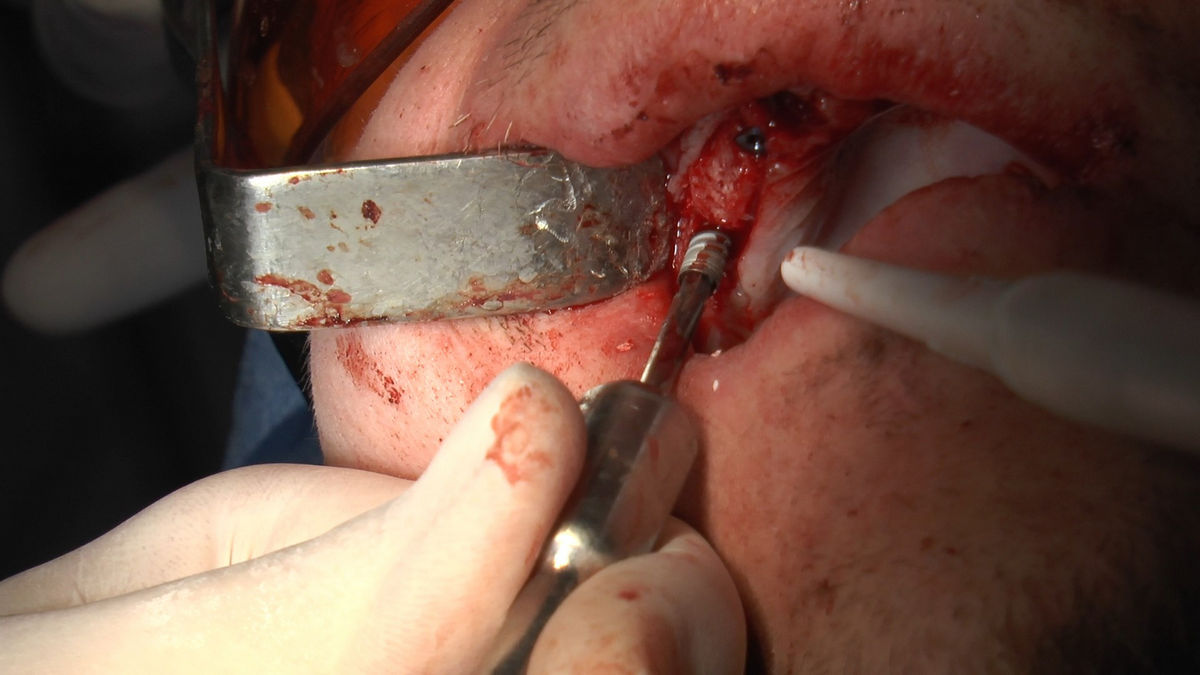

Tuż przed 100 Rocznicą Odzyskania Niepodległości, 9 i 10 listopada 2018 roku, kursanci VI Sezonu Practiculum Implantologii odbyli 7 Sesję. Dwa dni intensywnego szkolenia poświęcone zostały na zabiegi z zakresu chirurgii implantologicznej. Kursanci wykonali szereg zabiegów u Pacjentów pod kierunkiem Mentorów – dr n.med. Violetty Szycik i dr n.med. Magdaleny Kisłowskiej-Syryczyńskiej. Jak zwykle nie zaliczały się one do najłatwiejszych. W większości były przeprowadzone w arcytrudnych warunkach wynikających przede wszystkim ze stanu tkanki kostnej oraz stanu zdrowia, co wymagało precyzyjnego planowania. Z zabiegów skorzystało 17 Pacjentów, także z zastosowaniem znieczulenia ogólnego w formie sedacji dożylnej. Wszczepiono 23 implanty, wykonano zabiegi natychmiastowej implantacji po mnogich ekstrakcjach, przeprowadzono zabiegi augmentacji oraz 3 zabiegi sinus lift z zastosowaniem preparatów kościozastępczych i PRF. Wszystkie zabiegi przeprowadzane zostały zgodnie z planem i dużym stopniem samodzielności, który odpowiada zakresowi poszerzających się umiejętności szkolących się lekarzy. W panelu edukacyjnym Sukces Twojego Biznesu odbyły się pierwsze zajęcia z NLP. Kolejna 8 sesja już na początku grudnia.